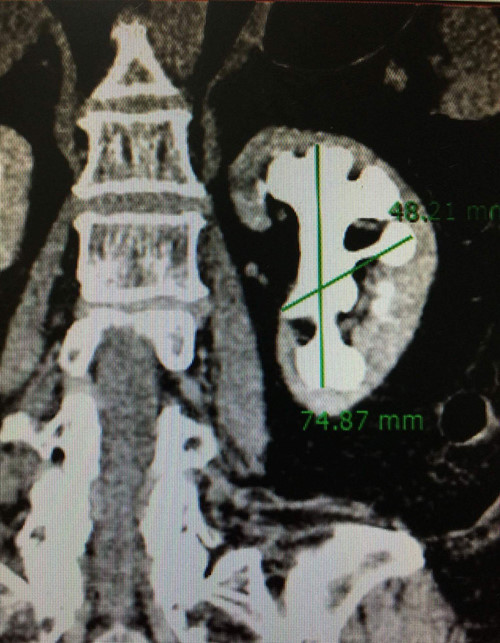

“Người bệnh bị sỏi san hô, kích thước 74 x 48 mm, to như củ gừng, chiếm hết toàn bộ thận và các đài thận trái. Đây là trường hợp sỏi thận phức tạp, hiếm gặp. Tên gọi sỏi san hô là do viên sỏi lấp đầy toàn bộ các nhánh đài thận, nhìn như một tảng san hô dưới biển”, bác sĩ Đức nói.

Hình chụp sỏi san hô, kích thước 74 x 48mm, chiếm hết toàn bộ thận và các đài thận trái của bệnh nhân